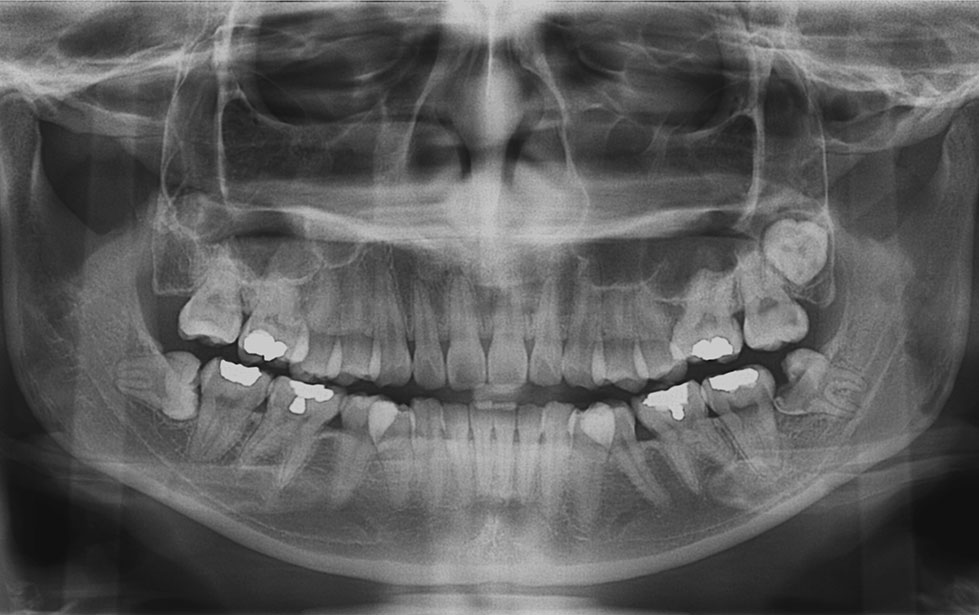

AI X-ray Detection & Automated Dental Charting

Ever wonder what your dental x-ray really shows? With our AI technology, you can now see it more clearly than ever.

The AI analyses your x-ray images within seconds and highlights areas that may need attention, such as tooth decay, impacted tooth, bone loss and etc. These are shown directly on your x-ray image, helping you understand what is going on at a glance.

The system also automatically updates your dental chart, which is part of your dental records, saving time and ensuring every detail is properly recorded.

• Clear, colour-marked visualisation on your x-ray